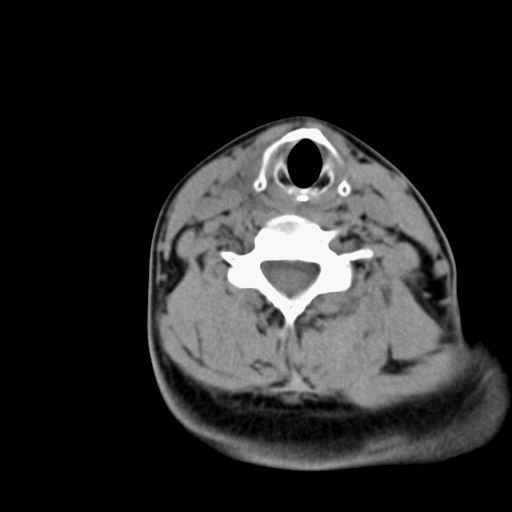

标题: CT23947 右颈部触及00.5x1.5cm质硬长形肿块,疼痛 [打印本页]

标题: CT23947 右颈部触及00.5x1.5cm质硬长形肿块,疼痛

甲状腺右叶占位病变,建议增强扫描。

甲状腺占位  定性有时很难 但无论癌还是腺瘤 还是手术比较好!以下是甲状腺占位的ct鉴别诊断

ct对甲状腺病变的诊断作用

确定病变范围,判断有无部属淋巴腺转移,甲状腺肿物没有可靠的征象鉴别良、恶性,如有部属淋巴结肿大、喉返神经麻痹、甲状软骨或其它喉软骨破坏等表现,则有利于诊断恶性。钙化不是鉴别良、恶性的依据。